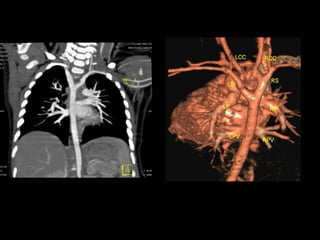

• There is extensive thrombosis of infrarenal segment of aorta, extending upto its bifurcation; into both common iliac

arteries causing total block in aorta and only minimal opacification of common ileac arteries bilaterally.

• Left renal artery is also blocked.

• Left kidney is small in size.

• Inferior mesenteric artery is not opacified.

• Bilateral external and internal iliac arteries reveal good contrast opacification from collateral of lumbar, intercoastal

and inferior epigastric arteries.

• Its superior ventral branches (i.e) coeliac and superior mesenteric artery are normal.

• Right renal artery is normal.

• CT scan of reveal Lehriche’s syndrome seen as block in infra renal abdominal aorta with blocked left renal artery.